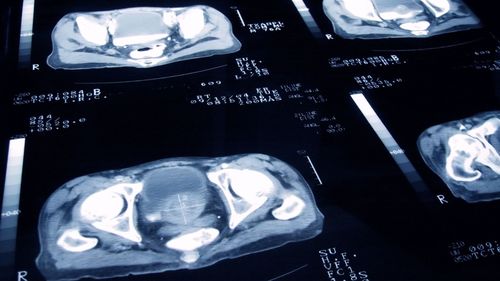

Cancer death rates fall to historic low - as types with biggest drop in fatalities revealed

Cancer death rates in the UK have fallen to a historic new low, Cancer Research UK has announced.